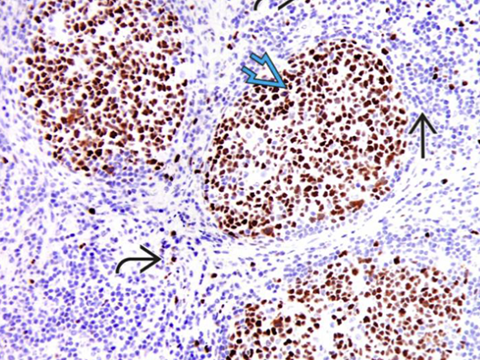

Immunohistochemical stain for Bcl-6 highlights centrocytes and centroblasts in the reactive germinal centers (open blue arrow) Mantle zone lymphocytes (straight black arrow) are negative; rare or scattered interfollicular lymphocytes (curved black arrow) are positive for Bcl-6. - Ki67 looks similar